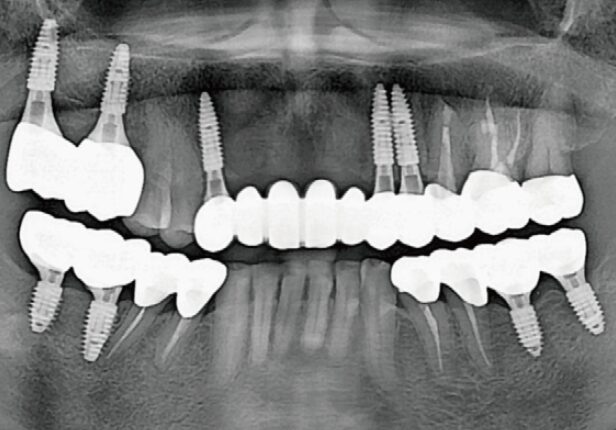

Panorâmica Final da Coroa

Ponte ARi caso de estudo